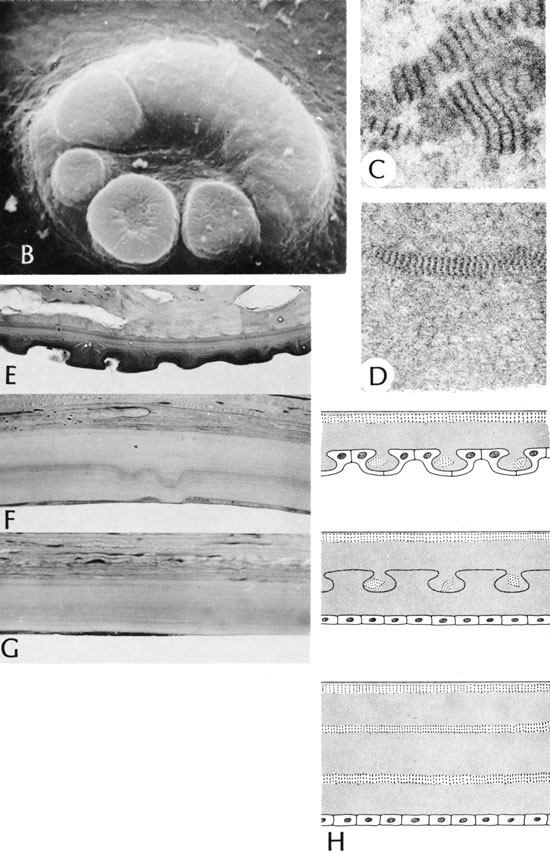

56. Polack F, Graue E: Scanning electron microscopy of congenital corneal

leukomas (Peters' anomaly). Am J Ophthalmol 88:169, 1979.

57. Kuper C, Kuwabara K, Stark W: The histopathology of Peters' anomaly.

Am J Ophthalmol 80:653, 1975.

58. Lee C, Yue B, Robin J: Immunohistochemical studies of Peters' anomaly.

Ophthalmology 96:958, 1989.